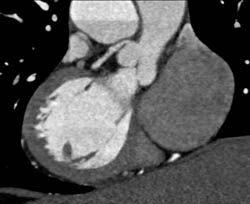

Coronary Artery Anatomy for LAD in Various Renderings